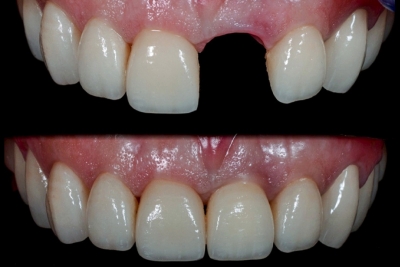

Ugradnjom implantata određenog dizajna i postizanja njihove visoke stabilnosti u viličnoj kosti u mogućnosti smo da potpuno ili parcijalno bezube pacijente obskrbimo privremenim nadoknadama, krunicama i mostovima koji se izrađuju unutar 24 sata posle implantacije. Time odmah nakon hirurškog zahvata možemo estetski rehabilitovati pacijenta sa izgubljenim zubom u prednjoj, estetskoj regiji ili mostovima na tek ugrađenim implantima kod bezubih pacijenata. Time se period čekanja za kvalitetnu oseoitegraciju značajno olakšava a pacijent ne prolazi kroz višemesečnu fazu potpunog nedostatka zuba, što je do skoro bila neminovnost.

Nauka je temeljno dokazala da pravilno odabran i opterćen implantat neposredno posle ugradnje ima istovetni dugoročni stepen uspeha kao i implanti koji su opterećeni posle perioda koštane integracije. Obavezna je pažljiva dijagnostika i planiranje, kao i pravilno odabran dizajn implantata, kako bi čak 80% pacijenata posle ekstrakcije zuba i ugradnje implanata u istom aktu mogli dobiti i privremene nadoknade. Privremene nadoknade omogućavaju funkcionalno i estetsko zbrinjavanje pacijenata do završetka integracije implantata, kada se izrađuje definitivna nadoknada. Ovaj pristup važan je svima koji imaju problem u socijalnim aktivnostima usled gubitka jednog ili više zuba, kao i pacijenti koji će zbog nedostatka svih zuba već posle operacije dobiti određenu estetsko funkcionalnu sanaciju i lakše proći kroz period ,,čekanja”